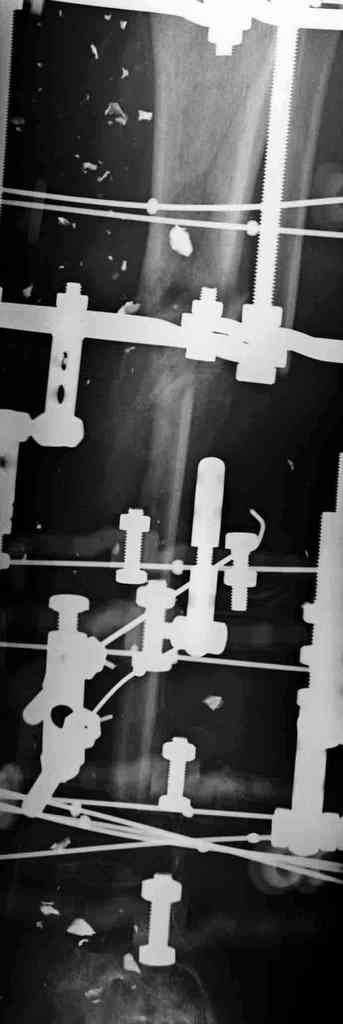

Реализовал описанную выше методику, и в итоге вот что получилось. Высылаю лишь прямые проекции,

в боковых тоже всё в тему.

Очень пригодились карбоновые кольца (Джолдас -огромное спасибо, я твой должник!!!), поскольку остеопороз дистального отломка был просто невероятный. На цифровом рентгене с трудом угадывались контуры.

Рентген в процессе перемещения - внизу карбоновые кольца, тракция фрагмента спицами с упором.